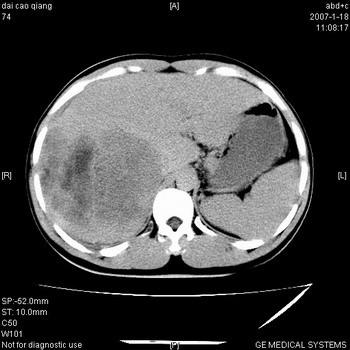

符合巨块型肝癌表现:

1、平扫低密度,增强后表现为快进快出。

2、动脉期可见迂曲的动脉供血血管

3、并可见门静脉右支癌栓形成

4、可见假包膜

5、腹主动脉旁结节影,考虑肿大淋巴结。

肝右叶巨大不均匀低密度肿块,前缘有假包膜,增强明显的呈快进快出表现,门脉右支有癌栓,病人虽然年轻但还是首先考虑肝右叶巨块形肝癌,病人血象高只能说有合并感染。不支持肝脓肿。